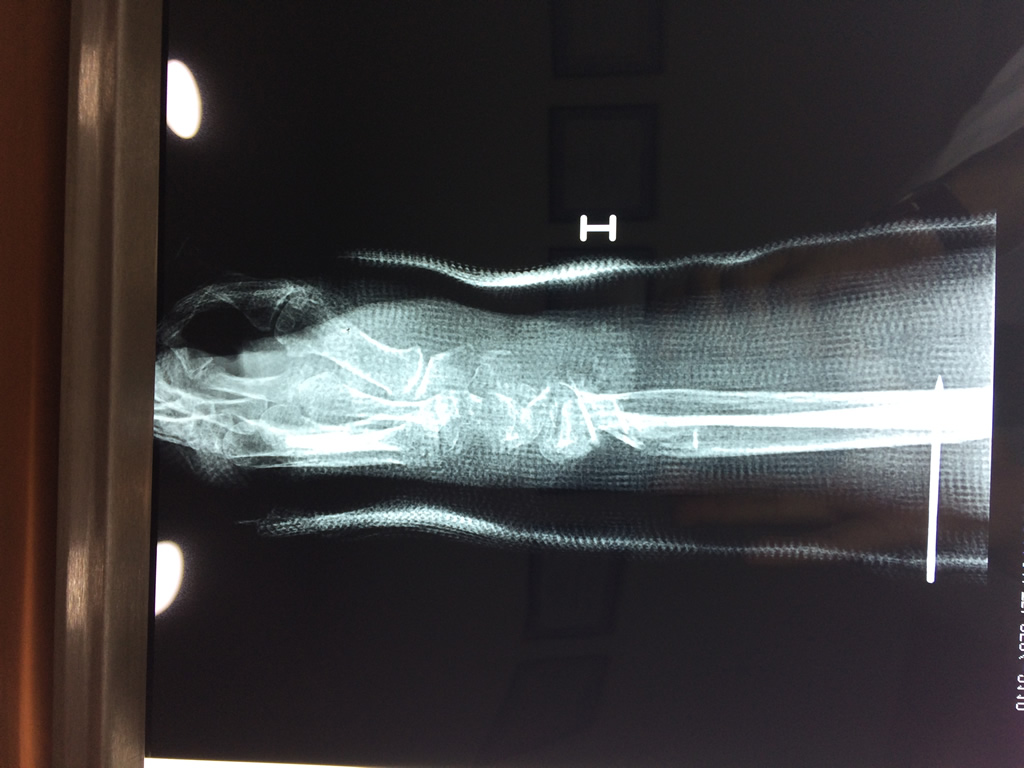

Los procedimientos más comunes en cirugía de la mano son aquellos destinados a reparar traumatismos, incluyendo lesiones de tendones, nervios, vasos sanguíneos, y articulaciones; huesos fracturados; y quemaduras, cortes, y otros daños de la piel.